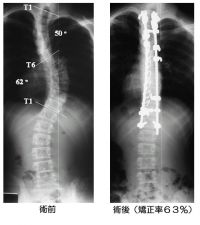

脊柱側湾症の矯正術は、背中側を切開して椎骨の後方に金属を固定して矯正する後方アプローチと、脇を切開して椎骨の前方(椎体そのもの)に金属を固定して矯正する前方アプローチがあります。

いずれも金属製のスクリュー(ネジ)やフック、ワイヤー、ロッド(金属の棒)などを組み合わせて使用します。70度くらいまでの側湾は、術者が得意とする方法であれば、効果についてはほとんど差がありません。80度を超えると高度な技術が必要となります。

私は腰椎や胸椎から腰椎の移行部については、前方アプローチで行います。前方では、椎体そのものを直接矯正できるので、狭い固定範囲で高い矯正効果が得られると考えています。後方よりも固定する範囲が少ないので、出血量が少なく、時間もより短くなるので、体への侵襲が少なくなります。また、最近では小さな皮膚切開、例えば12cmで5椎体の手術を行うこともできます。